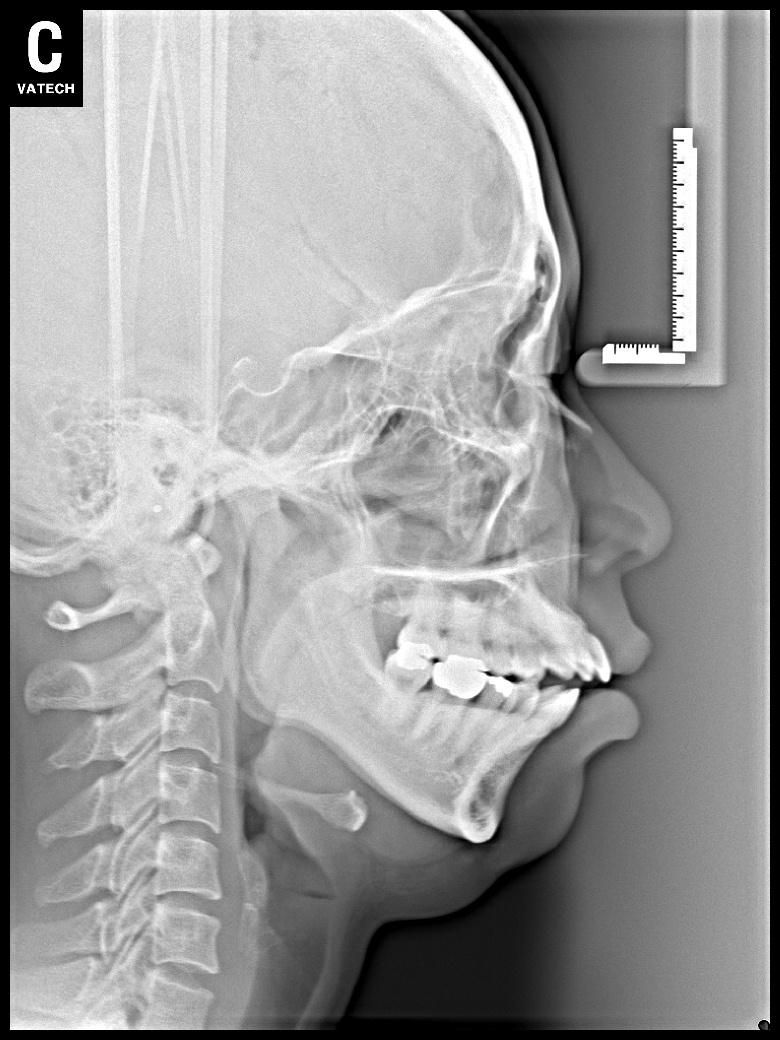

치료 전 사진입니다.